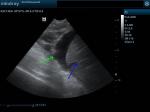

Έγινε υπέρηχος κοιλίας και καρδιάς. Στην κοιλιακή κοιλότητα βρέθηκε παρουσία άφθονου ασκιτικού υγρού.

( πράσινο βέλος ασκιτικό υγρό, μπλέ βέλος λοβοί του ήπατος)